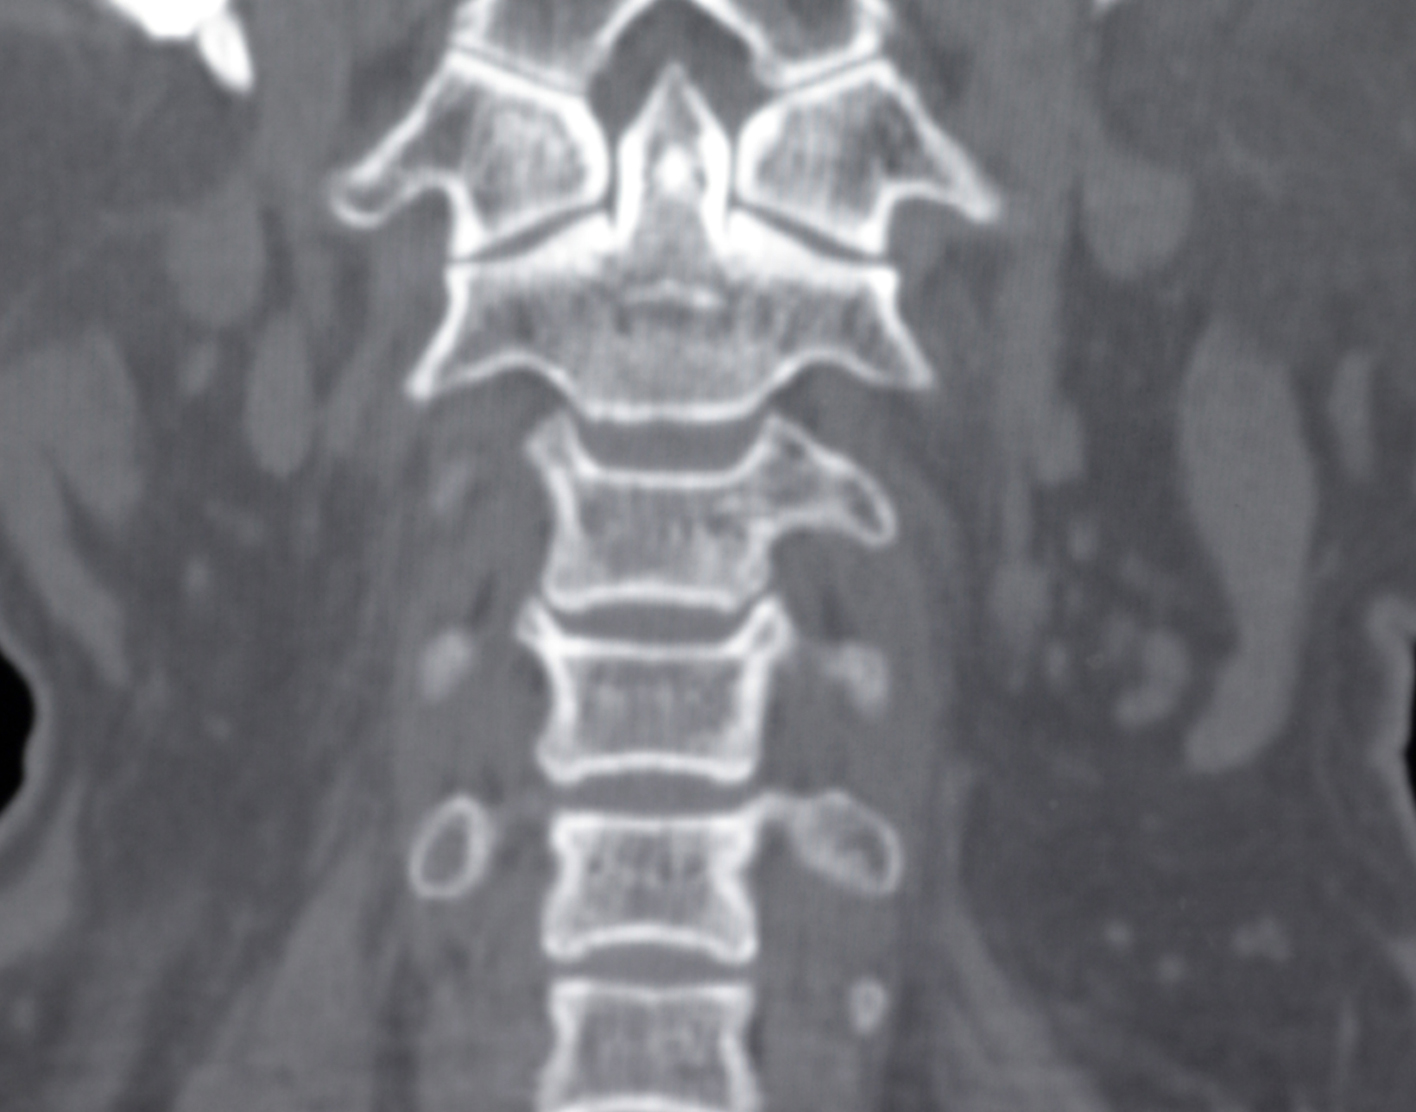

Cervical spine CT scan

A computed tomography (CT) scan of the cervical spine makes cross-sectional pictures of the neck. It uses x-rays to create the images.